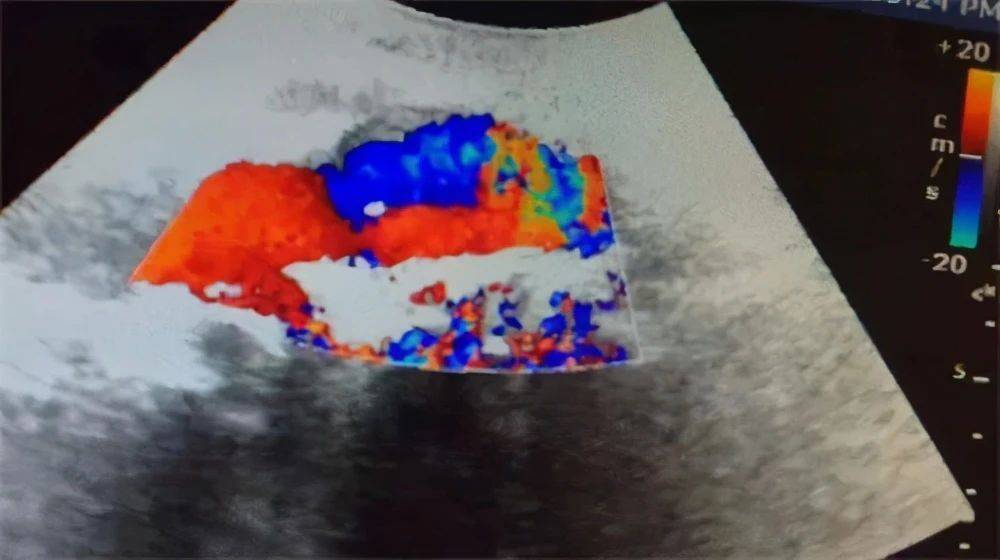

夹层动脉瘤:系指由各种原因造成的主动脉壁内膜破裂 , 血流进入主动脉壁内 , 导致血管壁分层 , 剥离的内膜片分隔形成“双腔主动脉” ,但Coady报道有8%~15%的病例并无内膜撕裂 , 这可能是由于主动脉壁中层出血所致 , 又称为壁间血肿(intramural hematoma) 。

腹主动脉长轴切面 , 腔内局部可见膜样强回声 。 夹层动脉瘤内可见真腔和假腔 , 真假腔的鉴别要注意几点:

1、不能单纯根据管腔的宽窄来判定真腔还是假腔 , 真腔可相对宽 , 也可窄 , 假腔亦如此 。

2、不能根据血流颜色判断真假腔 , 比如红色血流为真腔 , 蓝色血流为假腔是不对的 , 反之亦然

腹主动脉长轴切面 , 腔内可见膜样强回声 , 呈双腔征 。

真腔血流通畅 , 血流速度较快 , 血流颜色较鲜艳明亮 , 血流方向收缩期呈正向血流;假腔因前方受阻而血流缓慢 , 血流颜色偏暗淡 , 收缩期正向血流减少或呈反向血流;真腔因流速较快不易形成血栓 , 假腔因流速缓慢而容易发现附壁血栓 。 主动脉夹层的自然经过十分凶险 , 如果未能及时诊断治疗 , 病死率极高 。